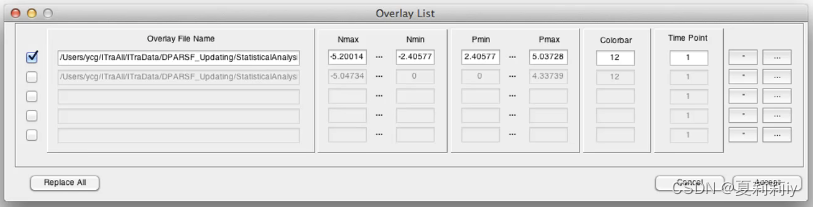

(1)Overlay

(2)Overlay Configure:是阈值设置,可以滑动也可以输入